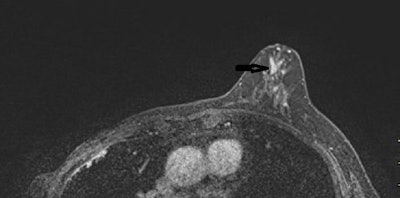

MRI showed ipsilateral abnormal enhancement in 54 patients (53%), revealing 46 lesions requiring excision (31 benign papillomas, five papillomas with atypia, two nipple adenomatosis, and eight cancers) and eight benign lesions not requiring excision. The team found no suspicious enhancement in the remaining 48 women (47%). Forty-two were followed up at one year with spontaneous resolution of the discharge, and six underwent surgery (revealing two benign papillomas).